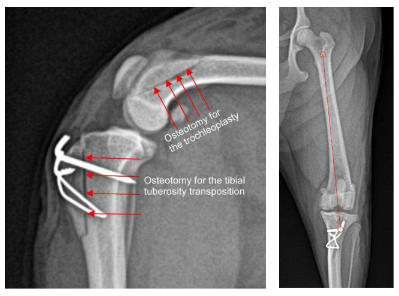

The figure above shows the osteotomy (cutting of the bone) where the trochleoplasty was made for a dog with medial patella luxation.

Tibial tuberosity transposition (TTT) for Patella Luxation

In order to address this, the tibial tuberosity is cut and shifted over (transposed), thus aligning the tibial tuberosity (and hence the patella) with the trochlear groove. The tibial tuberosity needs to be secured in this new location with pin(s) and wire to hold it in this location until bone healing is complete in 10-12 weeks. Once the tibial tuberosity has healed in this location the pins and wire could be removed, which is a minor procedure, but in most dogs the owners elect to leave the pins and wire in place.

The immediate post-operative radiographs (X-rays) for the same dog from above show how the tibial tuberosity has been re-aligned to center the patella over the center of the stifle (knee).